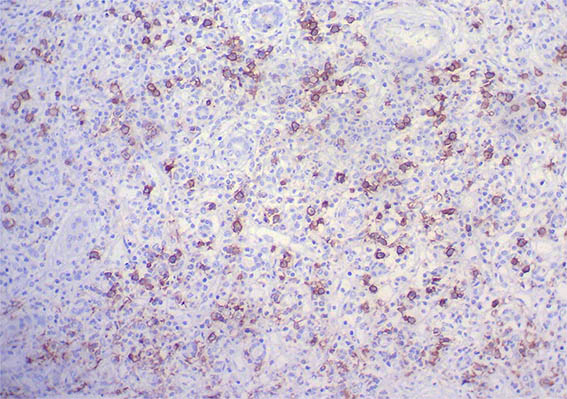

Figure 9. Immunohistochemistry for IgG, X200. Abundant IgG positive plasma cells, many of them IgG4: see images 11 and 12.

Figure 10. Immunohistochemistry for IgG, X400.